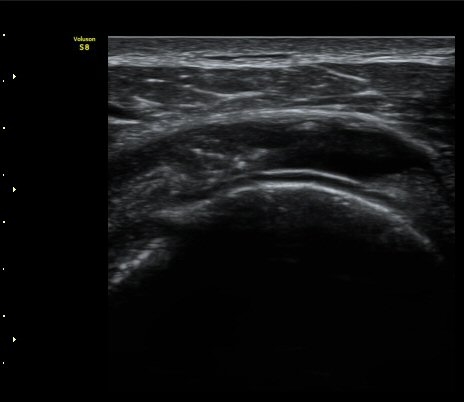

±Ø»ó°Ç Á¾´Ü¸é°Ë»ç¿¡¼­ ±Ø»ó°ÇÀÇ ÀüÃþÆÄ¿­°ú ±Ø»ó°ÇÀ» ¿¬°áÇÑ ºÀÇջ簡 Á÷¼± À¸·Î °üÂûµÈ´Ù(»çÁø 3, 4)